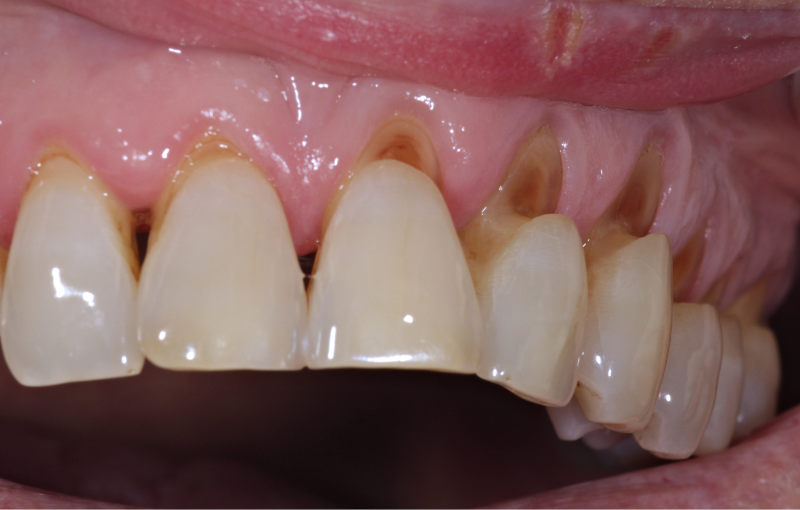

常見特徵如圖下:

- 牙齒靠近牙齦處出現V 型或凹槽

- 牙齦可能逐漸退縮

- 牙齒外觀變長、邊緣不平滑